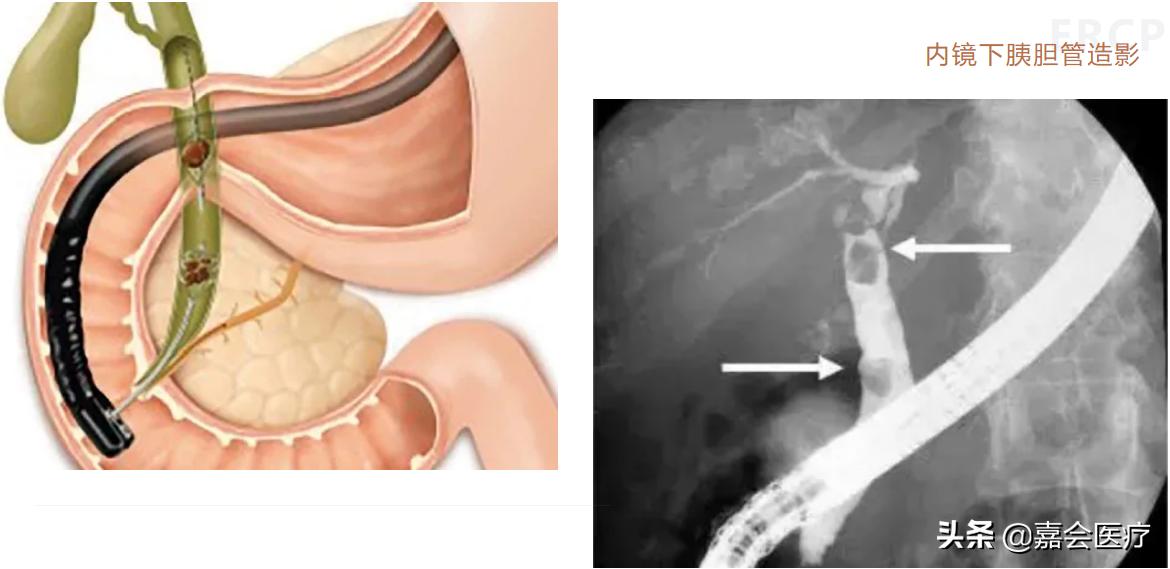

超声内镜,英文名Endoscopic Ultrasound,而ERCP是内镜下逆行胰胆管造影 (endoscopic retrograde cholangiopancreatography) 的简称。

ERCP是一种内镜技术,通过将特殊的上消化道侧视镜插入至十二指肠降部,经由十二指肠乳头(胆胰管在十二指肠的出口),使操作器械到达胆管和胰管,注入造影剂显影胆管或胰管,进而对胆管或胰管进行各种操作。